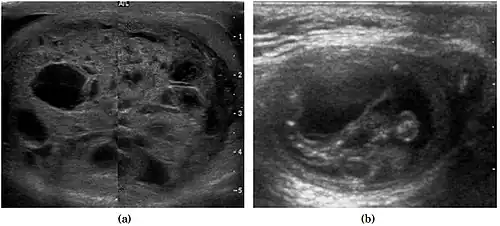

Teratoma Although teratoma is the second most common testicular tumor in children, it affects all age groups. Mature teratoma in children is often benign, but teratoma in adults, regardless of age, should be considered malignant. Teratomas are composed of all three germ cell layers, i.e. endoderm, mesoderm and ectoderm. At ultrasound, teratomas generally form well-circumscribed complex masses. Echogenic foci representing calcification, cartilage, immature bone and fibrosis are commonly seen [Fig. 5]. Cysts are also a common feature and depending on the contents of the cysts i.e. serous, mucoid or keratinous fluid, it may present as anechoic or complex structure [Fig. 6].

Fig. 5. Teratoma. A plaque-like calcification with acoustic shadow is seen in the testis. -

Fig. 6. Mature cystic teratoma. (a) Composite Image. Mature cystic teratoma in a 29-year-old man. Longitudinal sonography image of the right testis shows a multilocular cystic mass. (b) Mature cystic teratoma in a 6-year-old boy. Longitudinal sonography of the right testis shows a cystic mass containing calcification with no obvious acoustic shadow.